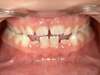

Le disjoncteur

Le disjoncteur est un appareil fixe composé de deux bagues fixées sur les 1ères molaires supérieures ou fixé à deux gouttières en résine scellées sur les molaires et prémolaires supérieures, et relié par un vérin médian. Il a pour but d’augmenter la largeur du palais et ainsi de corriger l’emboîtement dentaire latéral, de donner plus de place aux dents et d’aider à mieux respirer par le nez plutôt que par la bouche.

Le disjoncteur s’active à l’aide d’une clé à insérer dans le vérin et à tourner selon les consignes données par le Docteur Charlotte Eurin. Pour une démonstration, visionnez cette vidéo de la Fédération Française d’Orthodontie (FFO).

Disjoncteur sur gouttière